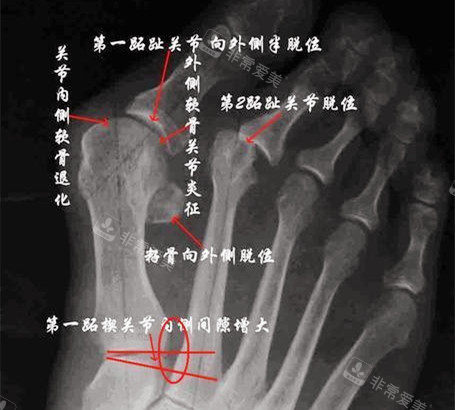

大脚骨X光片图片

大脚骨,医学上称为拇外翻,是一种常见的足部畸形。

它主要表现为大脚趾向外侧偏斜,头一跖骨内翻,使得大脚趾根部出现明显的凸起。

大脚骨脚步骨头透视图